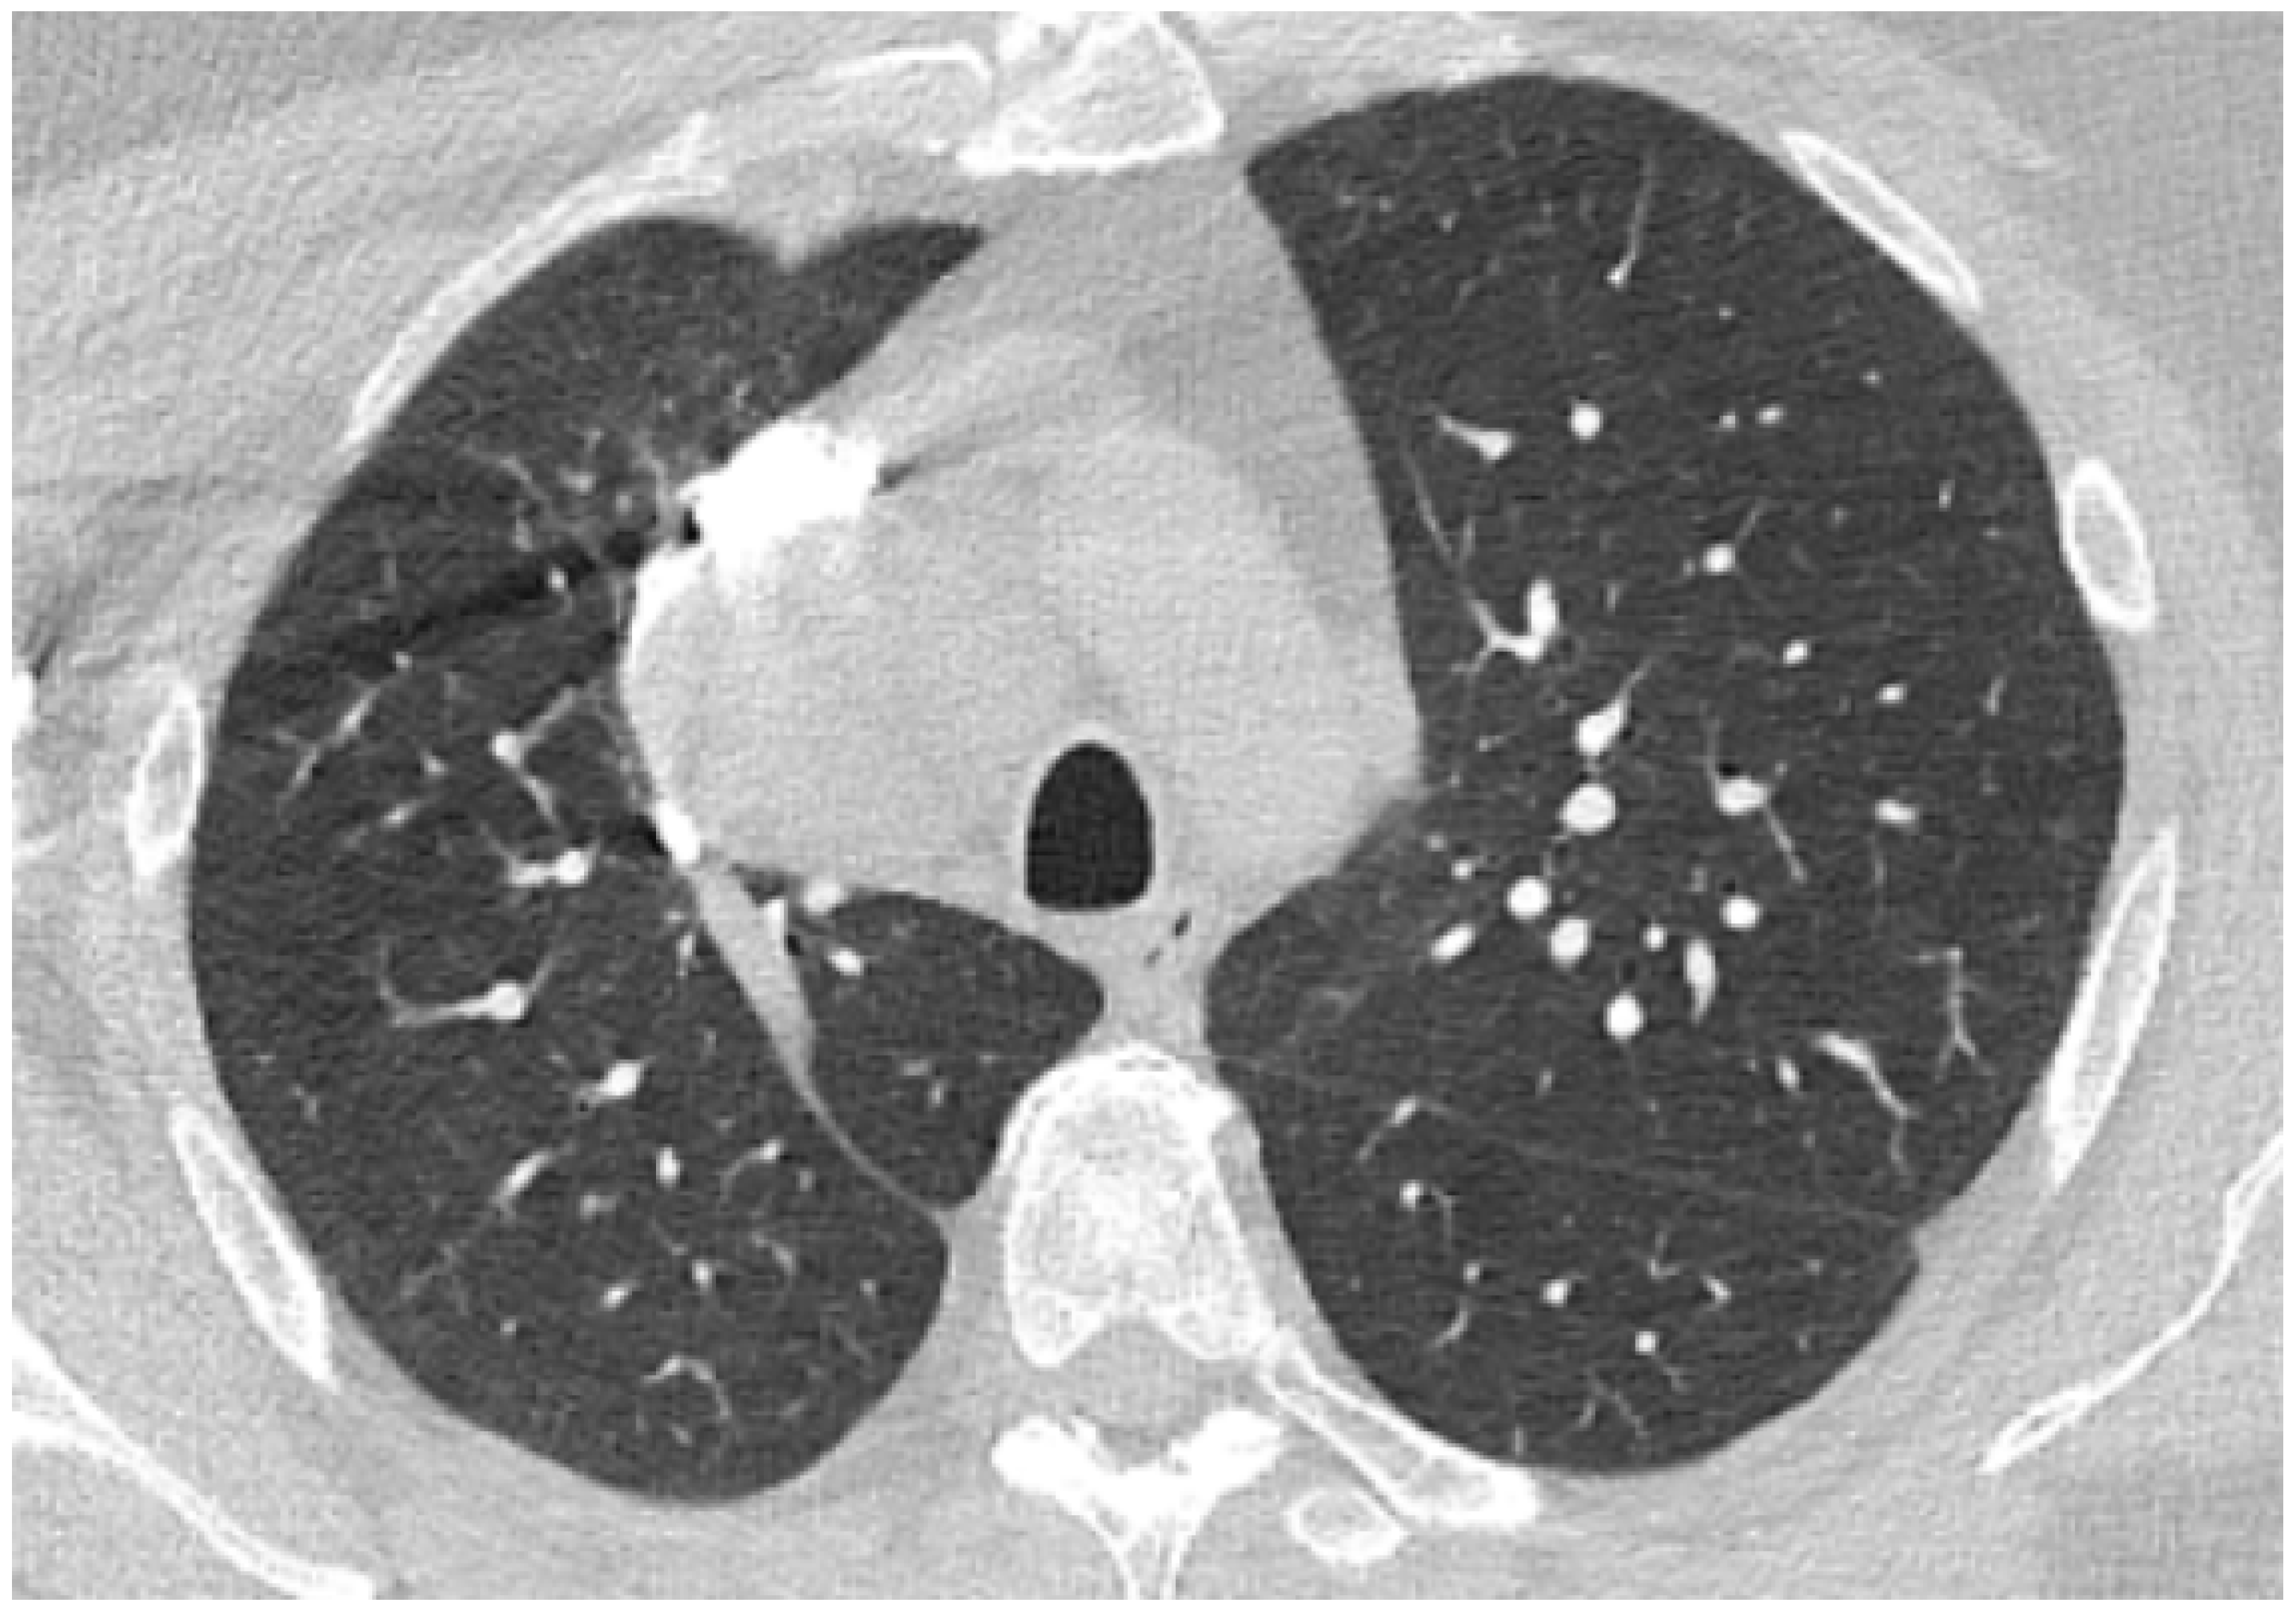

Considering possible sepsis of unknown origin, antibiotics were initiated with ceftriaxone. A sputum culture was positive for Klebsiella pneumoniae spp pneumoniae, and ceftriaxone was continued according to the antibiogram. Blood cultures taken consecutively were negative. During day 3, a thorax CT scan was performed, which showed fine areas of ground glass arranged peripherally and classified as minimal lung damage (Figure 5) and small bilateral areas of pleurisy with a maximum thickness of 10 mm in the right costo-phrenic recess. Methylprednisolone was given, with progressive decreasing of the dose over time. Standard medication for heart failure with a reduced ejection fraction was given [14]. The serum level of interleukin-6 was 2.32 pg/mL, which was considered to be normal [15]. The evolution was favorable: cardiac enzymes, inflammatory markers and procalcitonin continued to decrease and eventually were normalized. Kidney function was preserved. The muscle pain in the upper limbs subsided, with full recovery of functionality. Patient tested negative for SARS-CoV-2 infection on day 14 (RT-PCR).

Figure 5. Native chest computer-tomography in the context of confirmed SARS-CoV-2 infection: fine areas of ground glass arranged peripherally classified as minimal lung damage.